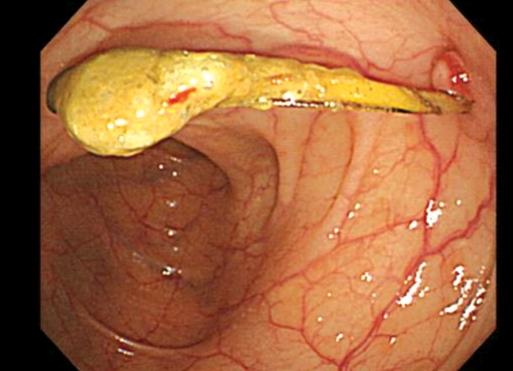

Foreign bodies in the gastrointestinal tract often cause serious complications, such as perforation, obstruction, abscess formation, or hemorrhage. This is a case in which a patient visited our hospital and complained of a vague lower abdominal pain that had been present for three months. She had an intrauterine device (IUD) inserted five years earlier. The abdominal X-ray, computed tomography and colonoscopy revealed that the IUD had penetrated into the descending colon. We tried to remove the IUD by colonoscopy but failed due to pain, so we removed the IUD surgically. Thus, we report a case in which a previously inserted IUD had penetrated into the descending colon and was surgically removed. We also present a brief review of the literature.